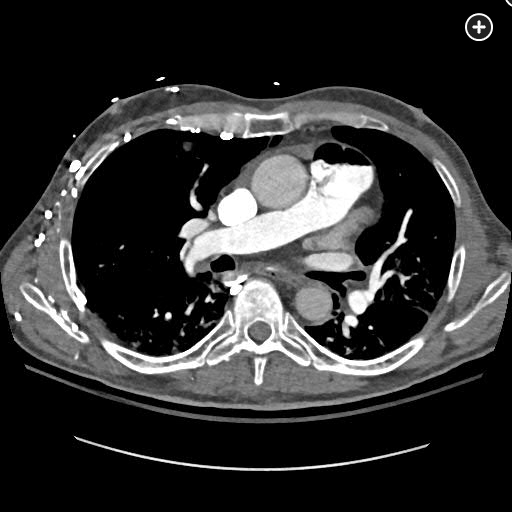

The CT pulmonary angiogram demonstrates a large volume of air in the right atrium, ventricle, and pulmonary outflow tract, with leftward bowing of the interventricular septum, suggestive of acute right heart strain (Figure 1, Figure 2, Figure 3, Figure 4).

CT image demonstrating air in the right ventricle with leftward bowing of the interventricular septum, indicative of acute right heart strain.